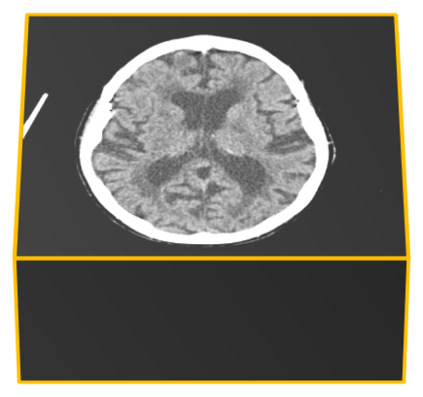

We present an effective method for Intracranial Hemorrhage Detection (IHD) which exceeds the performance of the winner solution in RSNA-IHD competition (2019). Meanwhile, our model only takes quarter parameters and ten percent FLOPs compared to the winner's solution. The IHD task needs to predict the hemorrhage category of each slice for the input brain CT. We review the top-5 solutions for the IHD competition held by the Radiological Society of North America(RSNA) in 2019. Nearly all the top solutions rely on 2D convolutional networks and sequential models (Bidirectional GRU or LSTM) to extract intra-slice and inter-slice features, respectively. All the top solutions enhance the performance by leveraging the model ensemble, and the model number varies from 7 to 31. In the past years, since much progress has been made in the computer vision regime especially Transformer-based models, we introduce the Transformer-based techniques to extract the features in both intra-slice and inter-slice views for IHD tasks. Additionally, a semi-supervised method is embedded into our workflow to further improve the performance. The code is available in the manuscript.

翻译:我们在RSNA-IHD竞争(2019年)中提出了一种有效的内爆出血检测方法(IHD),该方法超过了获胜者解决方案的绩效(RSNA-IHD 竞争(2019年),同时,我们的模型与获胜者解决方案相比,仅需要四分之一参数和10%的FLOP;国际HD的任务需要预测输入大脑CT的每个切片的出血类别。我们审查了北美辐射协会(RSNA)在2019年举办的IHD竞赛的5级顶级解决方案。几乎所有顶级解决方案都依靠2D共流网络和相继模型(双向GRU或LSTM)来提取虱内和肺间特征。所有顶级解决方案都通过利用模型共性能提高性能,而在过去几年中,模型数从7到31不等。由于计算机视觉系统,特别是以变压器为基础的模型取得了很大进展,因此我们采用了基于变压器的技术来提取IHDD任务的内切和相间观点的特征。此外,半超式方法已经嵌入我们的工作流程。